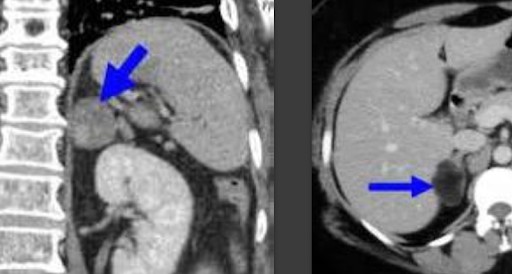

В свои 15 лет он весил больше 80 килограмм, постоянно болела голова, а любая попытка занять вертикальное положение приводила к скачку давления 200 на 120. Такие проблемы со здоровьем были связаны с образованием гигантской опухоли правого надпочечника. Гормоны, вырабатываемые ее, создавали нагрузку на сердце, постепенно истощая его.